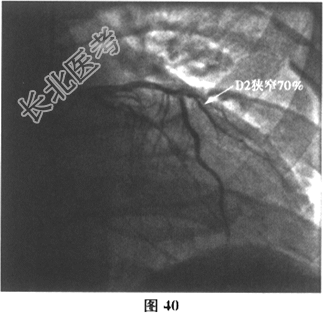

- 多项选择题6.[提示]运动负荷心电图试验示:最大运动功量3.3METs, Ⅱ、Ⅲ、aVF、V3~V4导联ST段压低0.05~0.1mV(图38)。查血小板聚集率:Ara14.57%, ADP36.55%。再次行冠状动脉造影:回旋支近端次全闭塞, LCX内支架内膜重度增生;LAD中段斑块浸润, 最重狭窄30%~40%,轻度肌桥压迫, 第二对角支狭窄70%;RCA近段斑块浸润, 如图39~图41所示。故于回旋支再次植入一枚支架(Promus Element2.75mm×38mm),如图42所示。